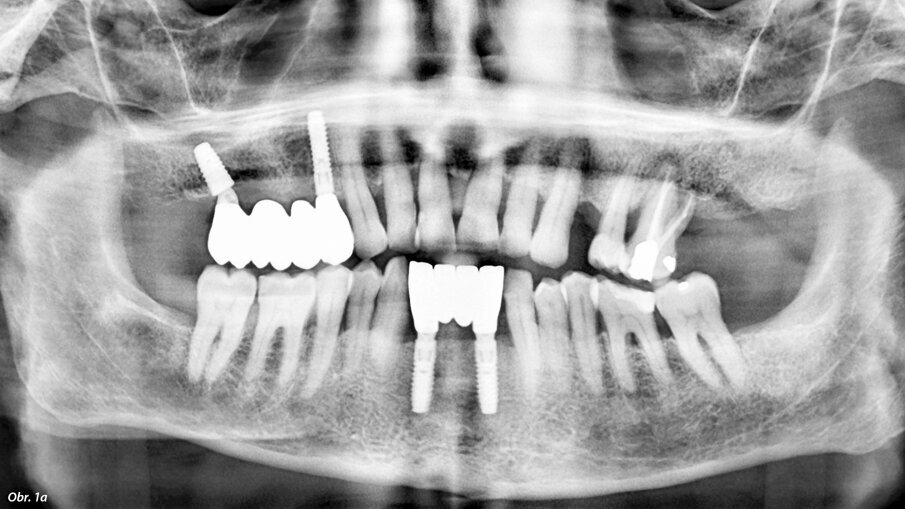

V dnešní době stále více implantujeme v místech s nedostatkem kosti pro klasickou implantaci. Nedostatek nabídky kosti často řešíme pomocí augmentačních postupů, stále častěji s využitím buněčné terapie – například kombinací augmentátů s destičkovými koncentráty (PRF, PRGF, PRP). Stále oblíbenějším řešením je využití stávající kosti pomocí skloněných implantátů. S meziodistálně skloněnými implantáty se lze často vyhnout problematickým strukturám, jako je foramen mentale nebo čelistní dutina, např. v rámci konceptu „all on four“. Často opomíjená možnost je vestibuloorální sklon implantátu. U pacientů s vhodnou anatomií čelisti můžeme tímto způsobem výrazně zjednodušit a zkrátit dobu terapie. Nejčastěji uplatňovaným postupem v horní čelisti je využití silné stěny čelistní dutiny pro zavedení implantátu, popřípadě navigace do neobvyklých kostěných struktur, které mohou vzniknout například kostním zhojením periapikálního granulomu. V dolní čelisti je pak zásadním aspektem zavedení implantátu tak, abychom se vyhnuli mandibulárnímu kanálu a vyřešili tak vertikální nedostatek kosti (obr. 1a, b).

Použitím tilted implantátů využijeme stávající kost bez nutnosti augmentace.